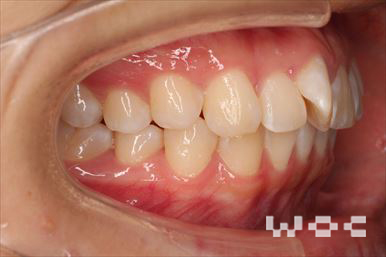

出っ歯舌側矯正

上下舌側矯正を希望。

通院状況や歯みがきの協力が良かったため、1年7ヶ月で治療を終えることができました。※装置と注意事項に関しては、大人の矯正装置一覧へ。

- 年齢:20歳女性

- 主訴:出っ歯が気になる

- 基本矯正料金:120万円

- 治療期間:1年7ヶ月

- 抜歯部位:上顎両側第一小臼歯